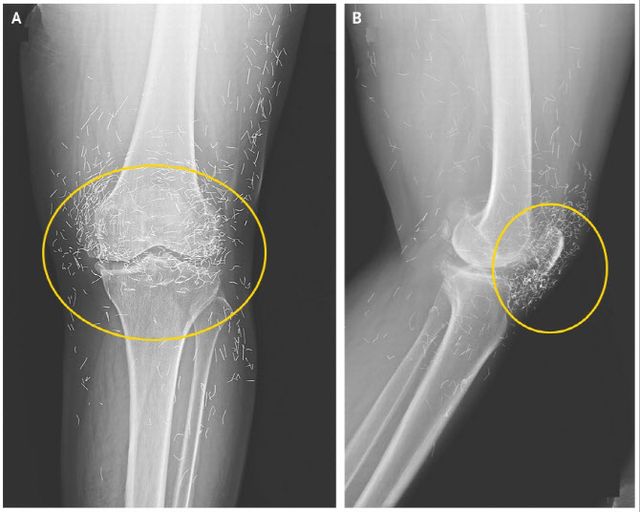

앞서 임상 의료분야 국제 학술지인 ‘뉴잉글랜드 의학 저널’에 65세 한국 여성 무릎을 촬영한 엑스레이 사진이 공개돼 화제를 모은 적이 있는데 당시에도 무릎 속에 수백 개의 바늘이 흩어져 있어 정체에 관심이 쏠렸고 이는 금침요법의 흔적으로 밝혀졌다.

이 여성은 평소 연골의 점진적인 손상으로 관절을 이루는 뼈와 인대에 염증과 통증이 생기는 퇴행성관절염을 앓아 항염증성 치료제 등의 약물요법을 받아왔다. 그런데 큰 효과가 없자 침술요법 쪽으로 치료방식을 바꿨다. 저널은 그녀가 여러 침술 치료 중 ‘금침 요법’을 받았다고 전한다.

통증 완화를 위해 계속 침을 주입하다 보니 어느새 개수가 수백 개가 넘었고 이것이 고스란히 무릎 속에 남게 된 것이다.

저널에서 미국 보스턴대학 방사선과 알리 게르마지 교수는 몸속에 이물질이 남아있는 경우, 염증 악화와 2차 감염 등으로 이어질 수 있어 무척 위험하다고 주장한다.

그는 “신체는 이물질이 들어오면 이를 제거하려는 방어 작용을 수행하기에 해당 과정에서 염증 등이 발생할 수 있다. 또한 침들이 몸속을 돌아다니면서 동맥과 같은 중요 부위를 손상시킬 수도 있다”고 강조했다.